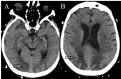

Although a neurological examination is fundamental to the evaluation of comatose patients, it is less reliable in a medically induced coma. A commonly misinterpreted finding in patients in a pentobarbital coma is altered pupillary reactivity secondary to an exaggerated ciliospinal reflex. Recognizing an exaggerated ciliospinal reflex in patients in a pentobarbital coma is important and may prevent unnecessary intervention. We present a patient induced in a pentobarbital coma for the treatment of status epilepticus who exhibited a nonreactive pupil secondary to an exaggerated ciliospinal reflex confirmed by pupillometry. We also discuss the anatomy of the ciliospinal reflex and literature regarding its clinical relevance.